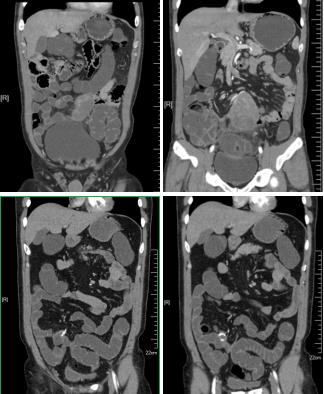

病例二 女,63歲,以持續(xù)性腹部疼痛不適半天就診。既往有冠心病15年、心房纖顫史5年余;高血壓5年。

采用心臟+主動(dòng)脈血管一站式檢查,可見(jiàn)該患者腸系膜上動(dòng)脈及其分支充盈缺損,同時(shí)顯示左心耳內(nèi)多發(fā)血栓, 隨時(shí)有血栓脫落的危險(xiǎn)。

全麻下行剖腹探查、 腸系膜上動(dòng)脈血栓取出術(shù), 病理顯示血栓樣組織機(jī)化。

患者術(shù)后第三天,由于右側(cè)肢體活動(dòng)障礙,語(yǔ)言受限,急查CT發(fā)現(xiàn)多發(fā)腔隙性腦梗塞,MRI檢查后明確左側(cè)急性梗死。

腸系膜上動(dòng)脈栓塞栓子多來(lái)源于心臟,也可來(lái)自于主動(dòng)脈壁粥樣硬化斑塊脫落。腸系膜上動(dòng)脈從腹主動(dòng)脈分出,主干口徑又較大,脫落的栓子易于進(jìn)入,在血管狹窄或分叉處導(dǎo)致血管栓塞。

臨床表現(xiàn)主要有“Bergan三聯(lián)征”1 、劇烈而沒(méi)有相應(yīng)體征的腹痛。2器質(zhì)性心臟病和并發(fā)心房纖顫的心臟病。3、胃腸排空障礙表現(xiàn)如腹瀉、 血便。

640層寬體探測(cè)器CT掃描速度快,可進(jìn)行大范圍心血管一站式檢查,快速排除血管病變,且由于探測(cè)機(jī)單元只有0.5mm,對(duì)于一些微小的病變也能清晰顯示。